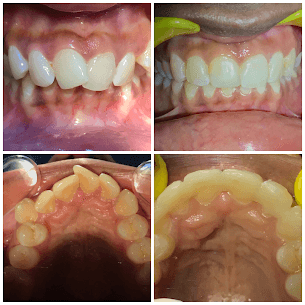

Fast Braces with Surgical Intervention

12-month treatment for 14-year-old with unerupted canine, including surgical exposure